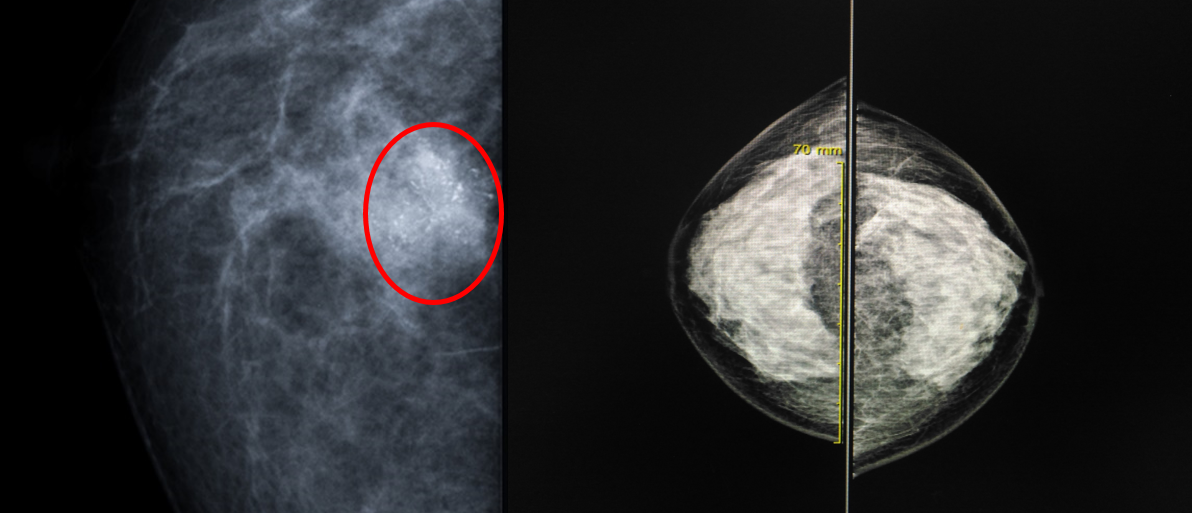

(좌) 동그라미 내부에 밝게 보이는 것이 석회화.

(우) 유선 조직의 밀도가 너무 높아 병변의 발견에 제한이 있다.

유방촬영술은 선별검사, 진단적 검사에 모두 유용하다고 알려집니다. 특히 유방암에서 자주 보이는 석회화를 찾아내는데 강점이 있습니다. 그러나 유방 자체의 밀도에 따라 민감도가 차이가 있습니다. 한국 여성들은 유방 밀도가 대체로 높아(치밀 유방) 한계점이 있는 부분은 있습니다. 만약 심한 치밀 유방이나 유방 관련 증상이 있다면 유방촬영술에 더해 유방 초음파를 시행 하는 것을 권고하기도 합니다. 유방 초음파와 비교해보면 각자의 장단이 있고 상호 보완적이기 때문에, 유방촬영술만 한다고 하여 검사가 불필요한게 아닌가 라는 의구심을 가질 필요는 없겠습니다. 유방 초음파는 무분별하게 하기보다는 의사의 판단하 필요하다면(유방촬영술에서의 치밀유방이거나 증상이 있는 경우) 시행 하는 것이 현재의 원칙이라 할 수 있습니다.